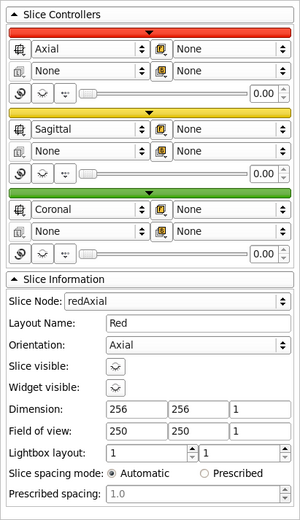

| qMRMLSliceWidget |

|

a 2D vtk render window with a controller |